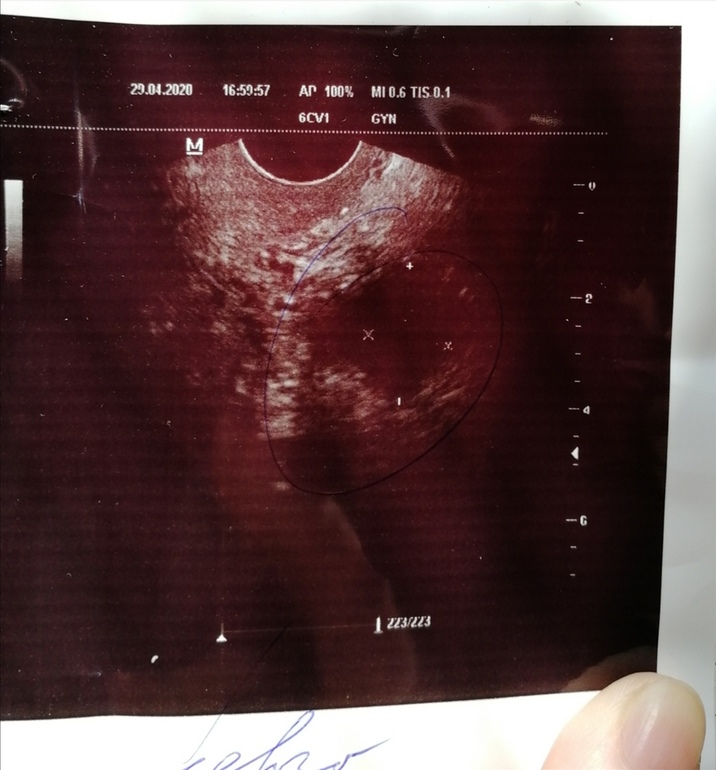

11 ДЦ - ДФ21мм , укол хгч 5000 ед

13 ДЦ - ДФ превратился в 14 мм))))) жидкости нет, ЖТ нет))))

Зато эндометрий не подвел))))))) аж 8 мм, а был 6.8. сответствует 1 фазе мц.

Ну уж глупый вопрос, может просто не успела образоваться жидкость и жт))) нет, там был четкий фолликул. 14 мм.

Легко. Вот и сейчас, на днях на снимке ЖТ, но врач упорно пишет ДФ. И честно сказала, что она нп знает, что это именно. И написала просто - анаэхогенное нечто, овуляция.

Запросто. Хотя даже я вижу на фото своего УЗИ именно ЖТ, но она видела ДФ.